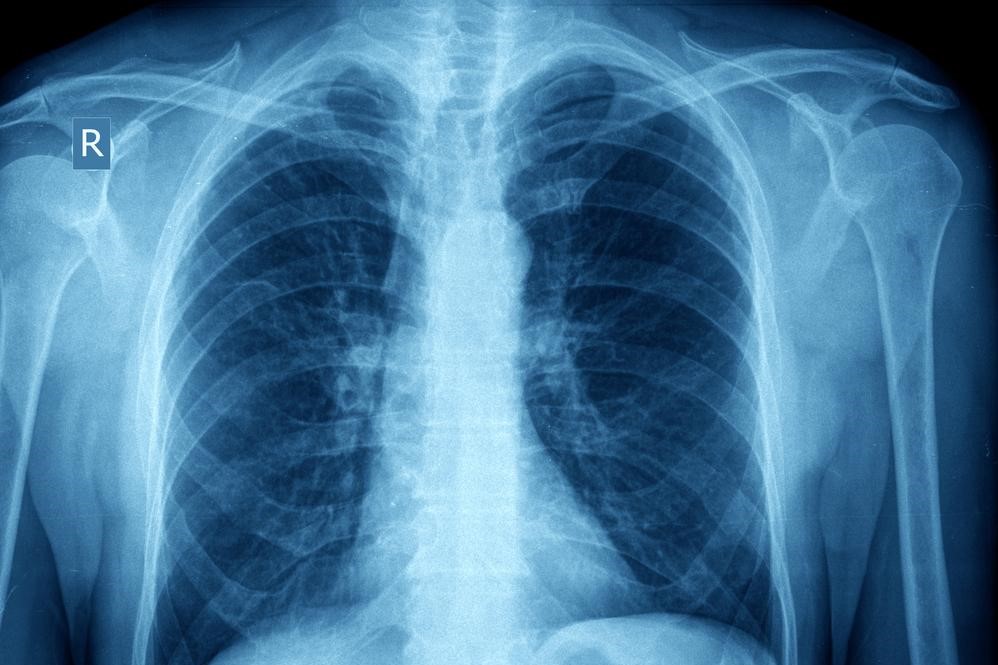

When a patient comes into contact with an asthma trigger, a chain reaction of events occur that leads to an asthma “attack.” The exposure to the trigger will cause the muscles that surround the airways to “clamp down” or contract, thus narrowing the spaces for air to travel through. In addition, the trachea and bronchial passageways will become inflamed with an increase in mucous production.

It is believed that patients always have some degree of inflammation in the lungs that make them more sensitive triggers. Chronic inflammation over time can lead to changes in the structures of the lungs and increased mucous production. Proper control of asthma can limit these effects.